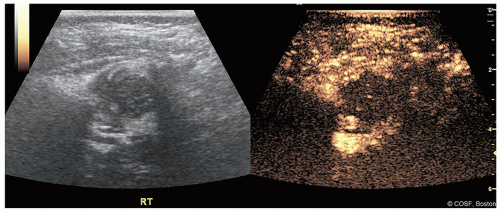

Intraoperative Contrast-Enhanced Ultrasound*

Ultrasound can be utilized intraoperatively to assess both hip reduction and hip perfusion

Hip reduction is assessed both prior to casting and in spica cast via an anterior/transinguinal approach (Figures 20.3,20.4,20.5)

This imaging has been validated against cross-sectional imaging1

Proximal femoral perfusion can be assessed using intravenous contrast

Perfusion can be graded as “good,” “partial decrease,” or “global decrease” in perfusion

Assessment is performed before attempted reduction and after casting as part of the reduction assessment (Figures 20.6 and 20.7)

Figure 20-7 ▪ Contrast-enhanced ultrasound after attempted closed reduction and decreased perfusion. (Courtesy of Children’s Orthopaedic Surgery Foundation.)

Preliminary data points to a strong correlation between decreases in perfusion and eventual development of proximal femoral growth disturbance (PFGD)